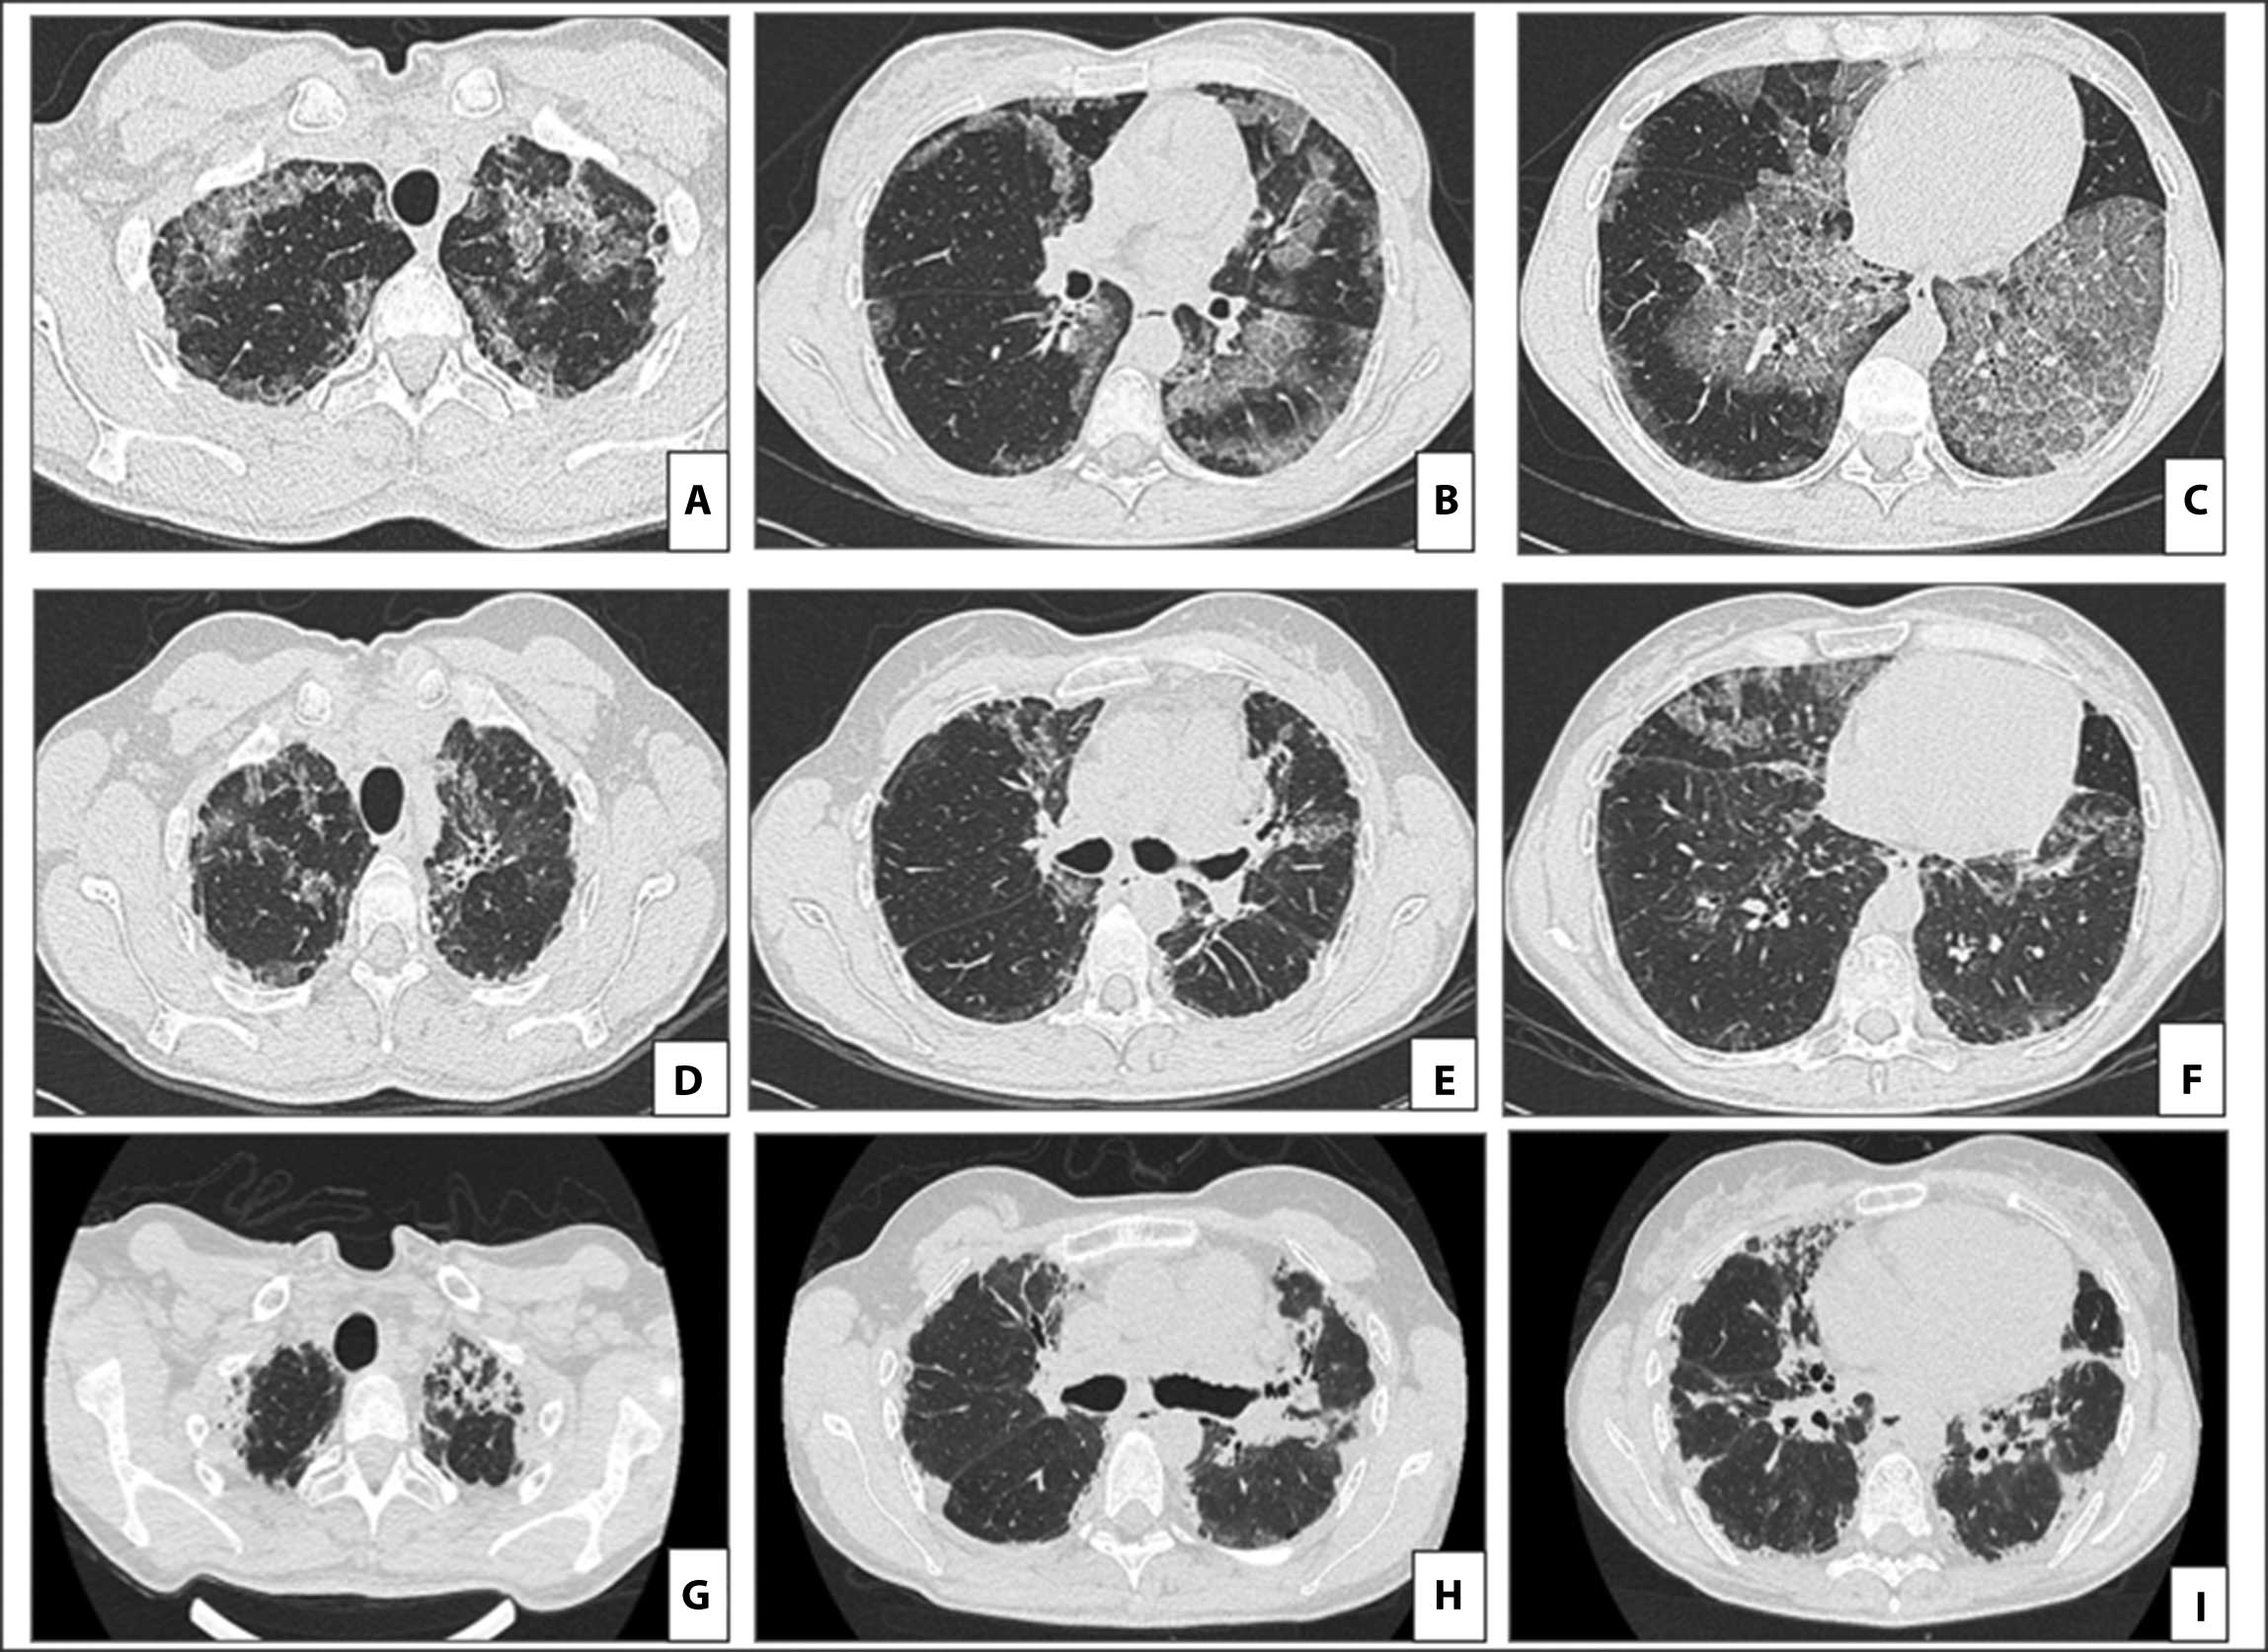

Background: Pulmonary alveolar proteinosis (PAP) has an unpredictable clinical course. Although usually benign, an association with pulmonary fibrosis is described in literature, with troubling therapeutic and prognostic implications.

Clinical case: We report the case of a patient affected by autoimmune PAP who developed pleuro-parenchymal fibroelastosis (PPFE) after 6 years of disease and underwent bilateral lung transplantation due to end stage respiratory failure.

18. Akira M, Inoue Y, Arai T, Sugimoto C, Tokura S, Nakata K, et al. Pulmonary Fibrosis on High-Resolution CT of Patients With Pulmonary Alveolar Proteinosis. AJR Am J Roentgenol 2016 ;207(3):544-51.

28. Hu-Wang E, Chelala L, Landeras L, Li H, Husain AN, Strek ME, et al. Pulmonary Alveolar Proteinosis--associated Pulmonary Fibrosis: Evolutional Changes and Radiologic-Pathologic Correlation. Radiol Cardiothorac Imaging 2023;5(5):e230040.